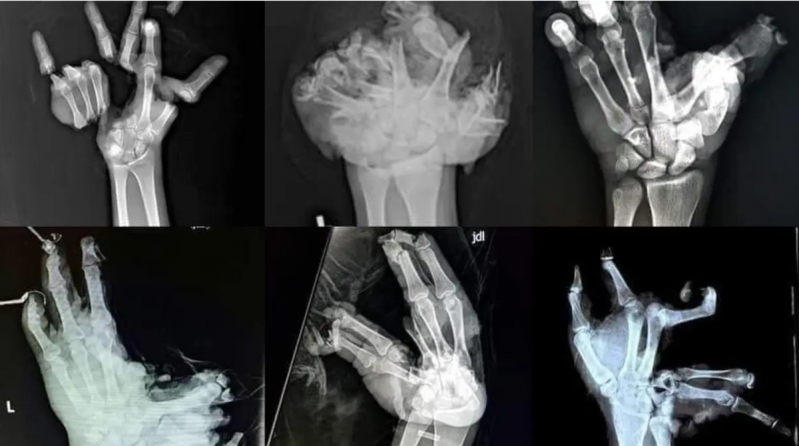

Iz udruge Prijatelji životinja već godinama upozoravaju na ovu nelogičnost. Koordinatorica projekata Snježana Klopotan Kačavenda navodi da su ovoga prosinca već zabilježene ozbiljne ozljede djece, čak i amputirani prsti: „Zabrana petardi i redenika nije učinkovita kada je gotovo šest dana krajem prosinca dopušteno korištenje jednako bučne i razorne pirotehnike. Nitko ne shvaća ozbiljno akciju MUP-a ‘Mir i dobro’ jer je radnim danima, bez ograničenja, dopuštena bučna pirotehnika, pa ni policija ne može razlikovati je li jaka eksplozija pod nečijim prozorom petarda ili dozvoljena raketa.”

Iako je zakonom maloljetnicima zabranjena kupnja, posjedovanje i uporaba pirotehnike, ozljede djece i ove godine dokazuju da sustav ne funkcionira. Prijatelji životinja smatraju da roditelji i druge odrasle osobe svjesno ugrožavaju zdravlje i život djece kupujući im pirotehniku kategorija F2 i F3, čija uporaba može uzrokovati gubitak prstiju ili vida: „Uz prijavu nadležnom centru za socijalnu skrb, takve osobe treba sankcionirati i zbog kaznenog djela povrede djetetovih prava, za što je predviđena kazna zatvora od jedne do osam godina ako nastane teška tjelesna ozljeda.”